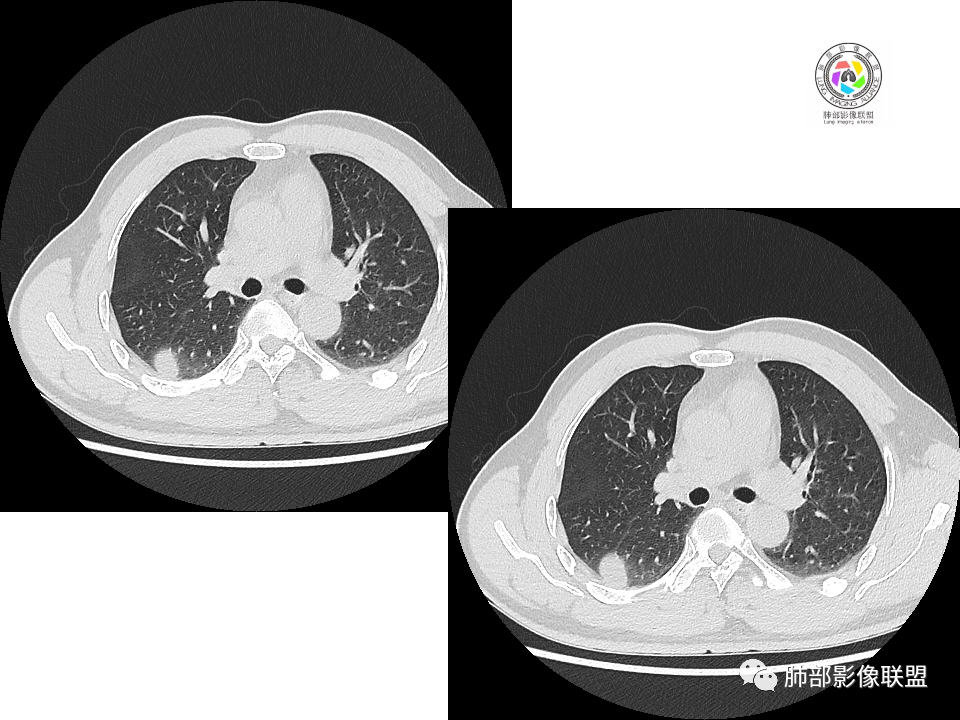

2.右肺下叶背段胸膜下块影,边界清楚光整,上下极见磨玻璃晕,未见明显分叶毛刺和棘状突起,未见胸膜凹陷或胸壁侵入。密度均匀,轻度不均匀强化。未见支气管进入。

3.右肺中叶外侧段胸膜下散在小片影,磨玻璃密度为主,边界不清,支气管相关。符合炎性特征!

4.右肺下叶基底段支气管血管束旁小结节影,边界清楚,强化不明显。注意,这结节在“遥远的”基底段。

显然本例焦点在于背段那个边缘光整的块影!

1.边缘光整干净,大病灶缺乏坏死等,不符合鳞癌影像学特征。尽管有吸烟史,还是偏年轻。

2.边缘光整,会是小细胞癌或是大细胞癌吗?小细胞癌的肺门纵隔淋巴结增大往往十分夸张,该患者不符合。

注意,基底段支气管血管束旁的小结节影,即便是淋巴结,也与背段病灶引流途径不符。